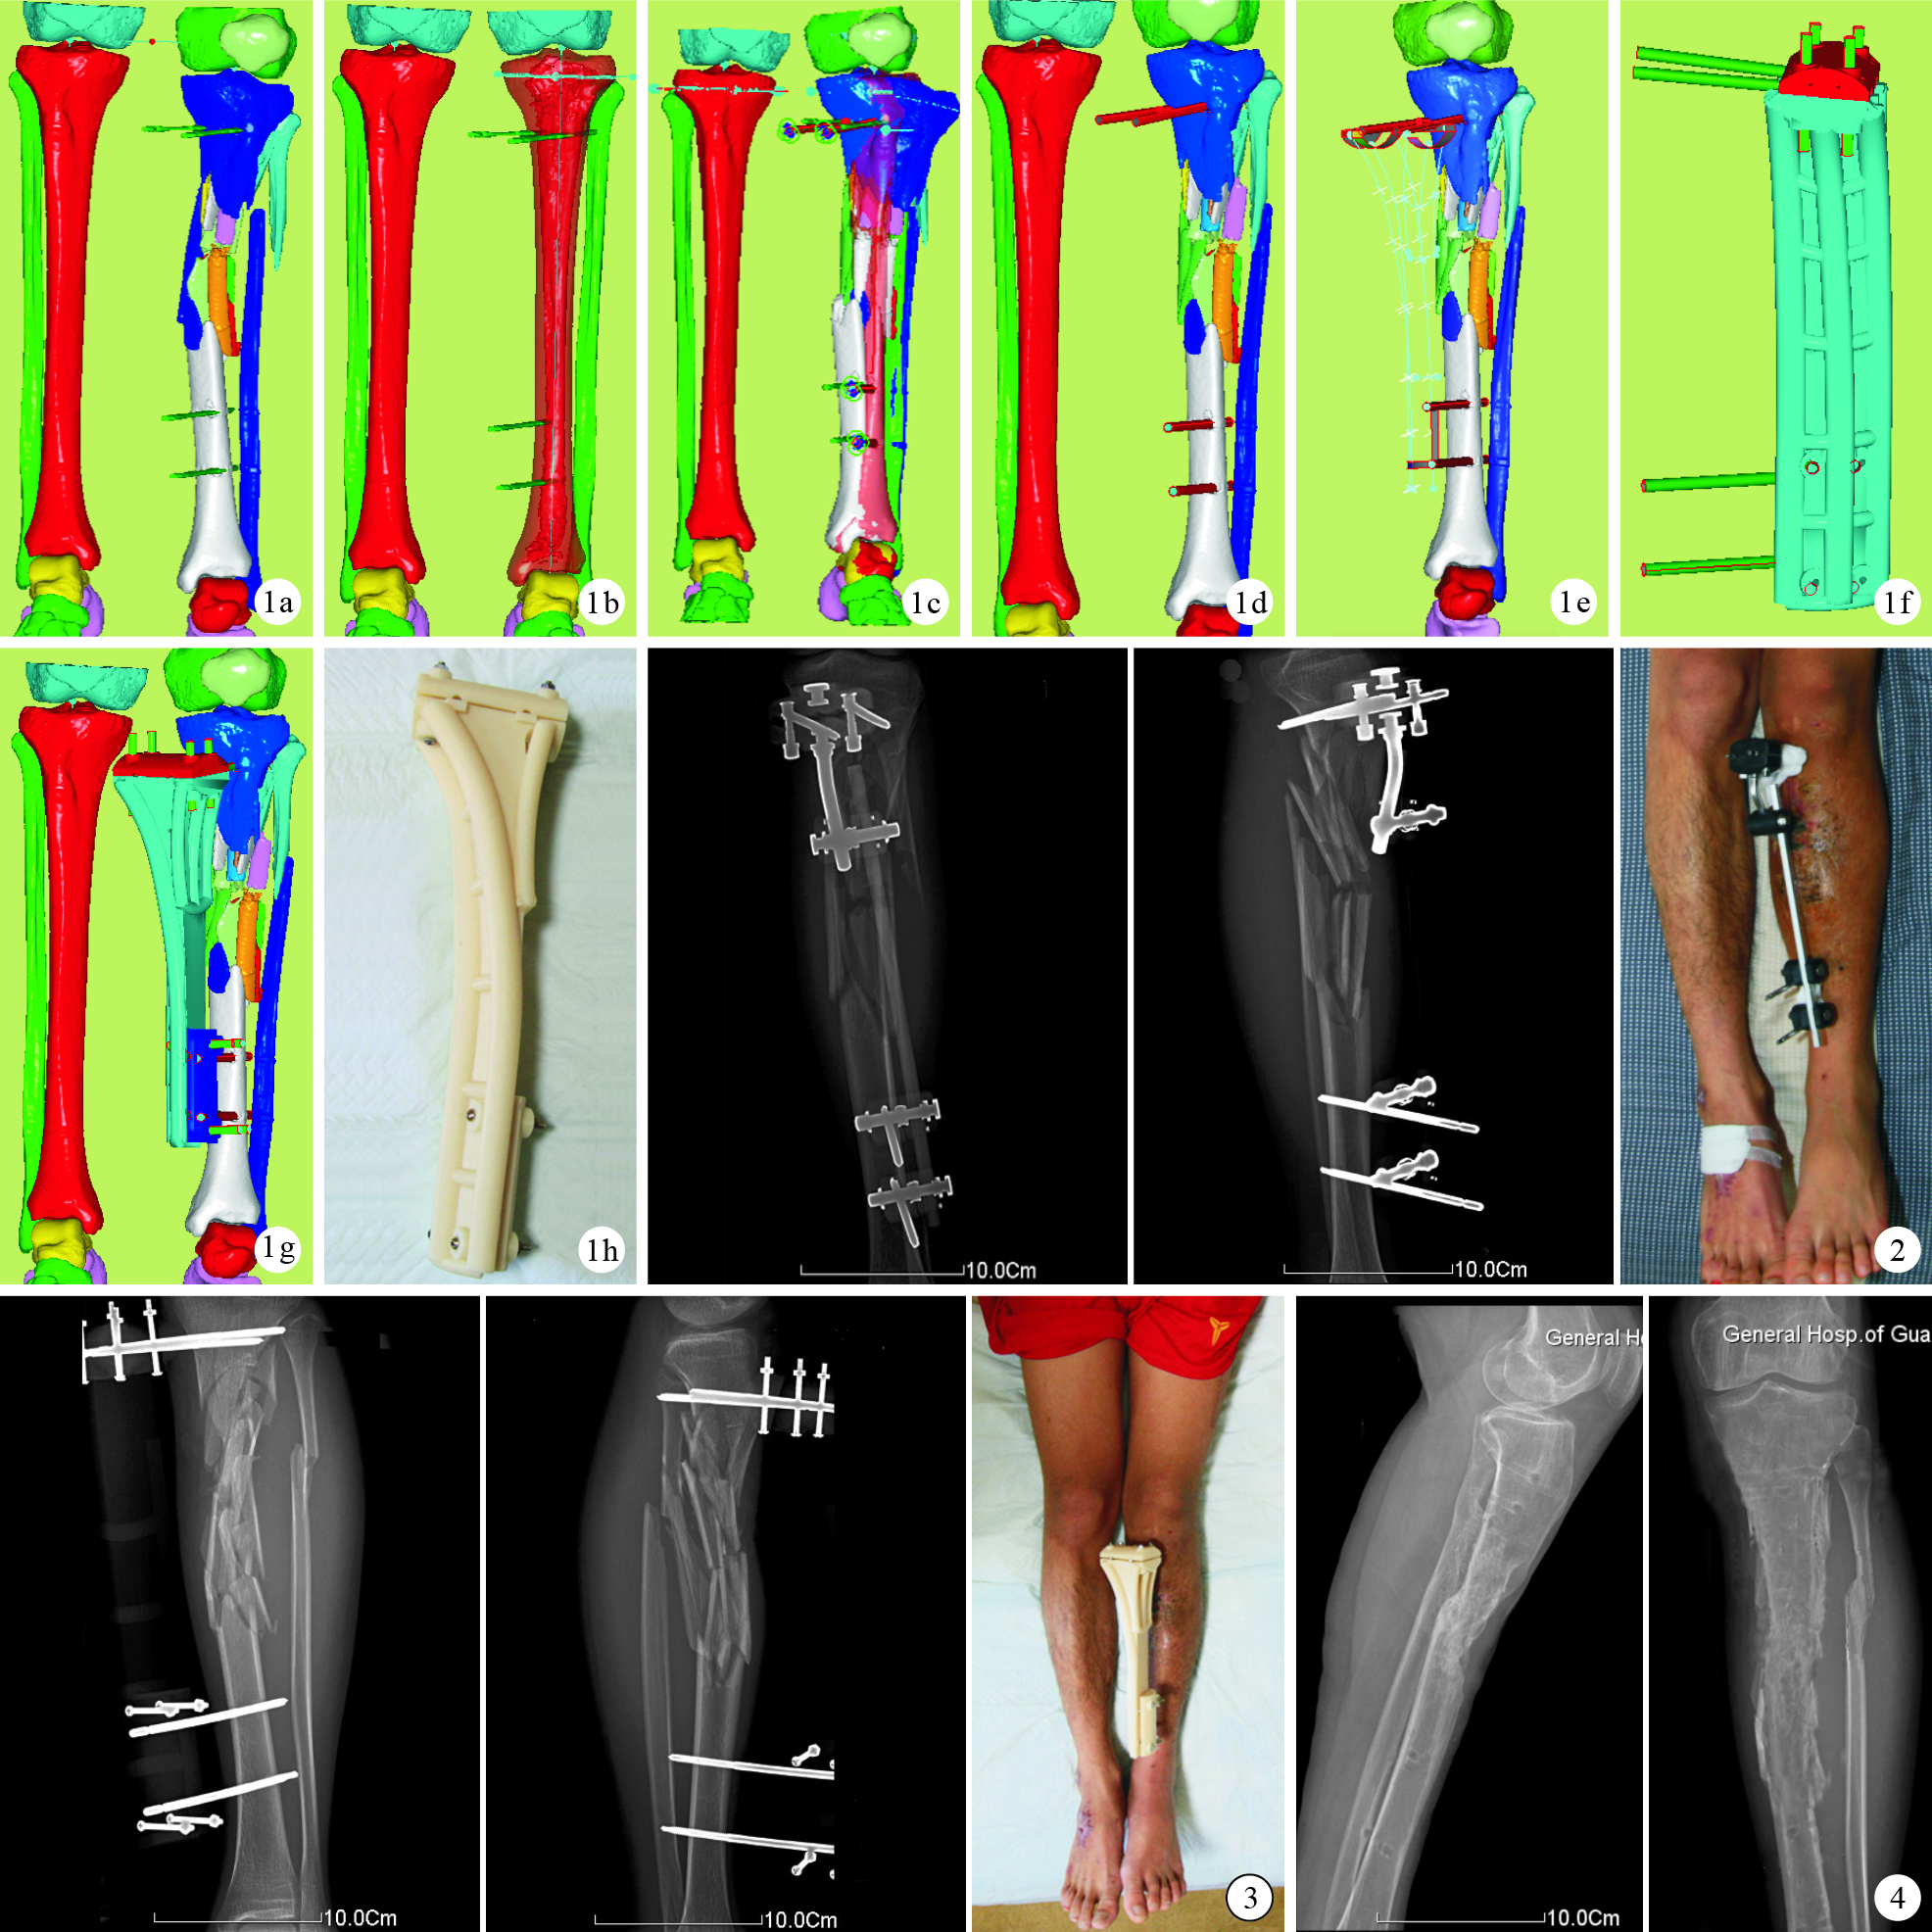

采用雙源電子計算機斷層掃描裝置連續掃描,獲得雙下肢二維數據,掃描參數:層厚0.625 mm、共1 024層、電壓120 kV、電流300 mAs;得到DICOM格式圖片1 024張并導入Mimics10.01軟件中。由于外固定釘密度較大,CT掃描會出現散射,因此先根據螺紋釘密度CT值利用“區域分割”功能設置灰度閾值(2 300~3 200)并創建蒙版,再通過“區域增長”功能將外固定釘圖像從原蒙版中分離,創立新蒙版,并作標識重命名。再根據骨組織的CT值設定骨灰度閾值(178~226),創立新蒙版,通過“蒙版編輯”、“區域增長”等方法將雙下肢各正常骨塊及骨折塊逐一分離,創立獨立蒙版并標識重命名。應用Mimics10.01軟件的高精度三維模型計算功能建立雙下肢三維模型。通過對模型的“光順”、“縮減三角面片”及“包裹”等功能進一步完善脛骨骨折三維模型[6]。見圖 1a。

將Mimics10.01軟件中的骨折三維模型數據導出為STL文件,并導入Imageware13.2軟件中,測量雙下肢力線及患肢的偏移度。通過鏡像原理,以健側肢體為模板創立患肢正常三維模型(圖 1b);利用獨立圖層模塊的旋轉、圖素任意位移,以鏡像模型作為參照,對齊下肢力線、模擬手術復位(圖 1c、d)。

在Imageware13.2軟件中模擬骨折復位成功后,根據復位后外固定針的位置選點,應用“畫線”、“曲面構建”功能,初步建立個性化外固定架計算機輔助設計片體模型。見圖 1e。將所建立的支架三維輪廓表面數據以IGES格式儲存,導入UG-NX8.0軟件中,應用“縫合”功能將各個曲面縫合成實體,進一步設計外固定針道,在轉折部位運用倒圓角操作,力學薄弱部位采用圓柱體弧形加強設計建立計算機輔助設計實體模型。為進一步減輕其重量,利于患者功能鍛煉同時節省打印耗材,在UG-NX8.0軟件中對支架主體采取中空設計,加強弧形連接桿采用實心設計,弧形連接桿設計可使支架所受應力分散,增加支架的強度和抗折彎能力。通過“順滑”、“美化”、“填充”以及使用有限元分析法優化及改進支架力學結構[7],得出支架最終效果圖(圖 1f)。支架模型以STL格式輸出后重新導回Imageware13.2軟件中,得出支架安裝后效果圖(圖 1g)。

外固定支架模型設計匹配完備后,在Imageware13.2軟件中以STL格式輸出,并導入Insight分層軟件中,選擇合適的模型打印擺放方式,對模型進行分層、添加支撐、編寫打印程序、形成打印文件,將打印文件輸出到Fortus400mc升級版3-D打印機中,進行自動打印。打印工藝采用熔融沉積成型技術(打印層厚0.127 mm,打印精度≤±0.127 mm)。為了提高外固定器的強度及減輕其重量,選擇高強度、熱熔點較高、生物性能良好的ABS-M30i材料[8-9]作為打印原料。打印完成后,從設備中取出實體模型,去除支撐,對模型進行打磨處理,得到支架實體(圖 1h)。

支架制作完備后,在患者床邊卸載原臨時外固定架(圖 2);牽引患肢,將原外固定釘釘尾套入外固定架預留的釘道中,并擰緊鎖定釘固定,安裝完成(圖 3)。整個安裝過程耗時約10 min,無需X線透視,以支架預留的釘道作為骨折端復位的體外參照,一次安裝成功。

3-D打印個性化外固定器安裝后復位效果良好,雙下肢恢復等長;復查X線片示遠折端向后成角糾正了37°、外翻成角糾正了4°,脛骨骨折端對位對線良好,下肢力線完全矯正,與軟件模擬復位后模型一致。術后第2天患者骨折端疼痛明顯減輕,可自主抬腿、屈膝鍛煉,術后1周可扶拐離床。術后未出現新的骨折移位,3.5個月后骨折臨床愈合,8個月后達堅強骨性愈合;左膝關節活動功能良好。見圖 4。